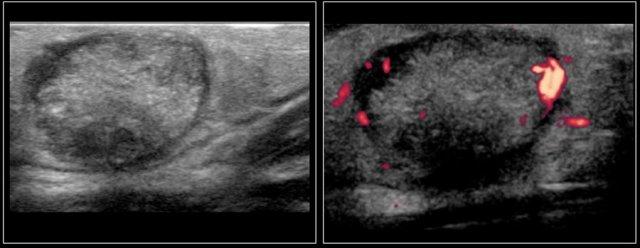

Hình ảnh của một bé trai mười bốn tuổi với khối sưng không đau ở cổ bên trái.

Siêu âm cho thấy nhiều hạch bạch huyết giảm âm phóng to, không có rốn hạch tăng âm.

Trên siêu âm, các hạch bị tổn thương có hình tròn, giảm âm đồng nhất và mất rốn hạch tăng âm bình thường.